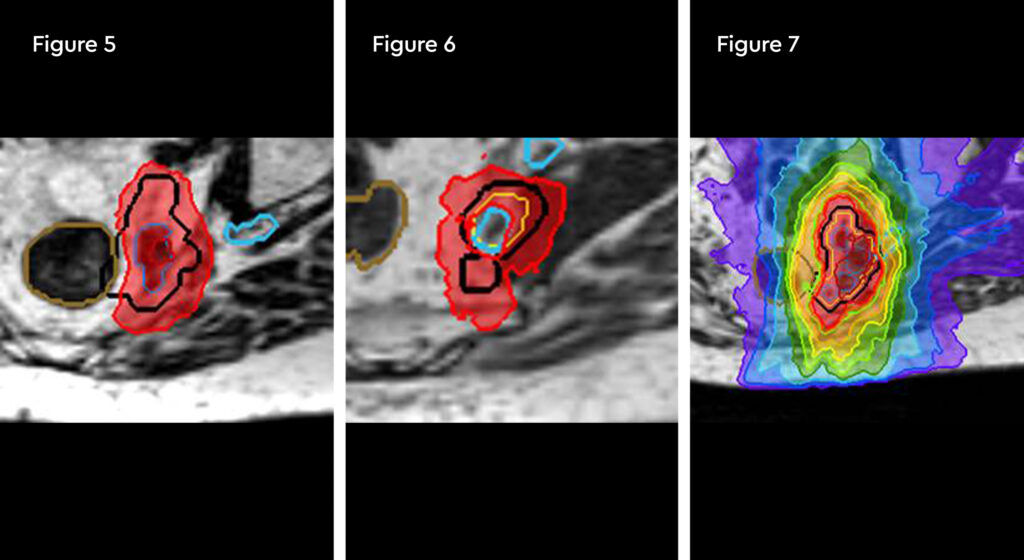

Figure 1 and figure 2 illustrate the typical interfraction movement as seen on the MRI scan. Figure 3 and figure 4 demonstrate the daily changes of the patient’s internal anatomy whilst figure 5 and figure 6 show the adaptive radiotherapy plan.

Fig 1: Internal anatomy during the planning MRI

Fig 2: Internal anatomy during first fraction of treatment

Fig 3: Changes in internal anatomy demonstrated by a smaller rectum on day 3 compared to the planning scan

Fig 4: Changes in internal anatomy demonstrated by a different rectum size on day 4

Fig 5: Radiotherapy plan

Fig 6: Plan adaptation. Tight conformality at rectal and prostate boundary is demonstrated by the arrow. Rapid reduction of high dose optimises dose delivery to the prostate and limit dose to the rectum, reducing the risk of long term toxicity.